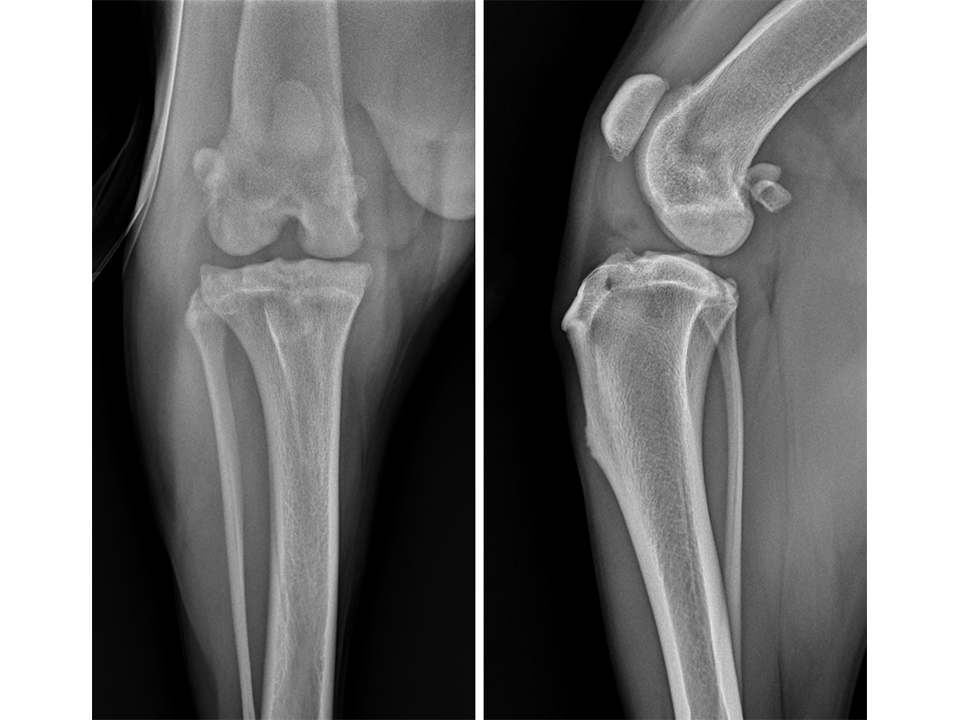

Radiographs of the right stifle (Fig 10) revealed moderate joint effusion and periarticular osteophytosis likely secondary to CrCL disease with concomitant MPL.

The right stifle joint was considered a suitable candidate for a tibial tuberosity transposition and advancement (TTTA) to stabilize the CrCL deficient stifle and realign the quadriceps mechanism with one surgical procedure. Preoperative TTTA planning was conducted as previously described and a 12 mm wedge and a size 7 plate were selected.